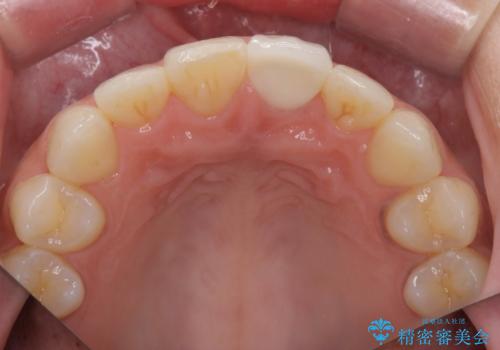

すり減った前歯の形態回復

- すり減ってしまった前歯の審美性の回復を希望され来院されました。

何度かレジン修復を試みたものの、脱離しやすく変色も気になる、とのことでセラミッククラウンによる審美性の回復を計画します。

右側は、クラウンにせず可及的に形態を整えることのみでの対応としました。

自然な色調のセラミッククラウンで審美性を回復することができ、大変満足いただけました。